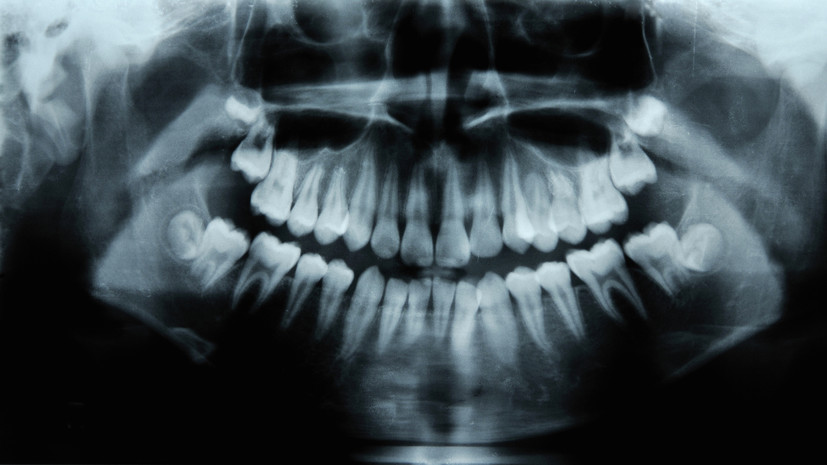

Стоматолог Баграмян: шаткость зуба может стать причиной для его удаления

В беседе с «Газетой.Ru» эксперт отметил, что при потере зубом опоры снижается его функциональность.

«При сильной шаткости зуб невозможно зафиксировать, и он подлежит удалению», — сказал врач.

По словам специалиста, также показанием к удалению зуба может быть воспаление в его корне, разрушение нерва, киста, гранулёма или абсцесс.

«Чтобы остановить распространение инфекции, зуб могут удалить», — добавил врач.